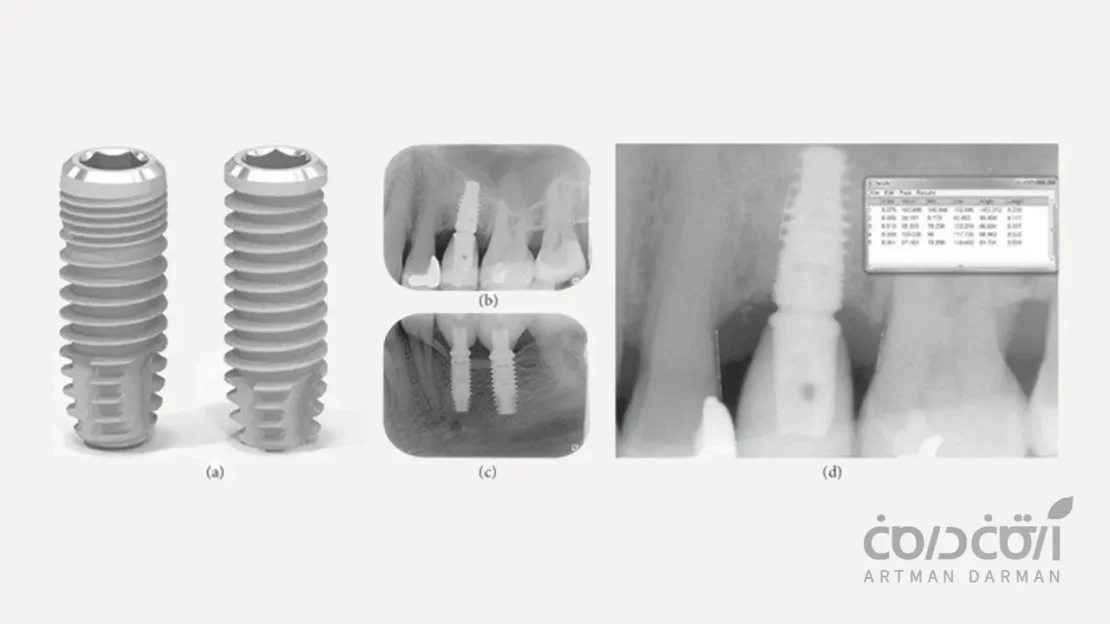

1. طراحی بدنه ایمپلنت و تنوع محصولات برای هر شرایط بالینی

یک سیستم ایمپلنت جامع، باید برای شرایط مختلف بالینی، راه حل مناسبی پیش روی ما قرار دهد. در این خصوص سیستم ایمپلنت sic سوئیس دارای خطوط تولید متنوعی است که به دندانپزشک اجازه می دهد بر اساس کیفیت و کمیت استخوان بیمار، بهترین گزینه را انتخاب کند. برای مثال:

- سری ACE: این لاین، ایمپلنت های استاندارد این شرکت هستند که برای اکثر شرایط استخوانی مناسب هستند. و طراحی بدنه آن ها به گونه ای است که ثبات اولیه عالی را فراهم می کند.

- سری MAX: این ایمپلنت ها با قطر بیشتر، برای قرارگیری فوری در حفره دندان های آسیاب (مولر) پس از کشیدن، طراحی شده اند و می توانند به خوبی فضای خالی را پر کرده و ثبات لازم را کسب کنند.

- سری Zygomatic: برای موارد بسیار پیچیده که تحلیل استخوان فک بالا شدید است، این سیستم ایمپلنت های بلند زایگوماتیک را نیز ارائه می دهد.